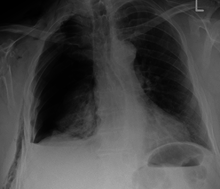

| An X ray showing multiple old fractured ribs of the person's left side as marked by the oval. | |